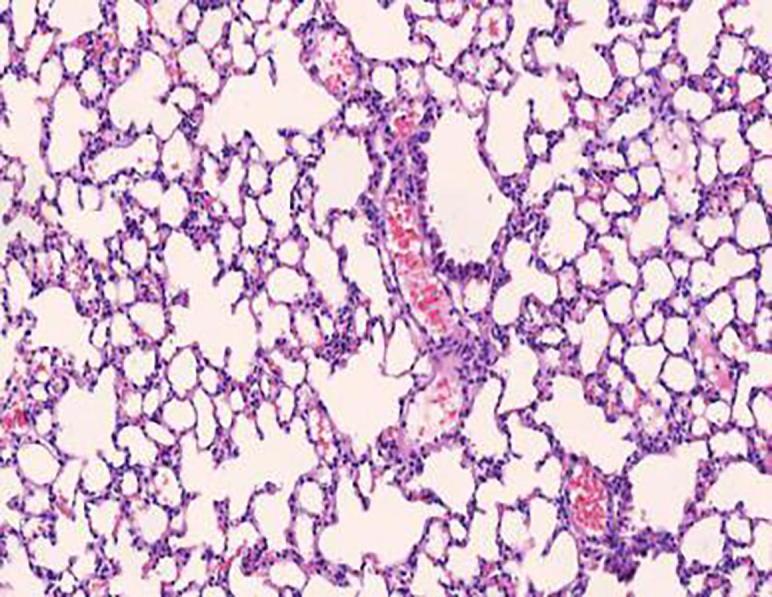

Compared with model group, the Schisandrae Fructus syrup groups can significantly increase the tidal volume of mice and decrease the respiratory frequency and the degree of bronchial stenosis ( < 0.01); The Schisandrae Fructus syrup groups can decrease the levels of NO and IL-6 in serum and improve the pathological changes of lung and bronchus in different degrees.

与模型组相比,五味子糖浆组可显著增加小鼠潮气量,降低呼吸频率及支气管狭窄程度(P<0.01);五味子糖浆组可降低血清中NO和IL-6水平,不同程度改善肺及支气管的病理变化。